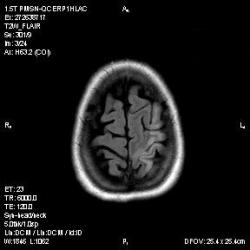

Из анамнеза - Женщина 45 лет. За год похудела на 15 кг (со слов матери), в последние месяцы случались эпизоды потери сознания. Онкозаболеваний и прочая в анамнезе нет. Сознание спутанное, из особенностей в анализах только подъем амилазы крови.

К сожалению, не владею методом КТ, но учитывая наличие неравномерного уплотнения в мозговых структурах с элементами очаговых "вкраплений", единственное, что приходит на ум - это рассеяный склероз. Хотелось бы уточнить, что беспокоило пациентку в течение последнего года кроме потери веса и эпизодов потери сознания? Была ли какая-либо очаговая неврологическая симптоматика? Отмечались ли какие-либо расстройства в двигательной или чувствительной сфере и т.д.? С уважением Helenmar.

И это точно не РС, т.к. характер очагов другой, ни один из них не копит контраст, нет субтенториальных очагов (извиняюсь, я этого в сообщении не указал), нет клиники.

"Раскрою" карты. Мы подумали о синдроме MELAS (mitochondrial encephalomyopathy, lactic acidosis and stroke) - дословно, митохондриальная энцефаломиелопатия, лактоацидоз и инсульт. В качестве дифференциальной диагностики можно было бы предположить вирусный энцефалит, но опять-таки, расположение очагов смущает - только с одной стороны и в абсолютно различных структурах.

В данном случае мы видим импульную последовательность FLAIR - режим с подавлением сигнала от воды, поэтому ликвор гипоинтенсивен, а также (вторая серия) - изображения, взвешенные по T1 после введения контрастного препарата. На T1 жидкость (ликвор) также представляется гипоинтенсивной. Зато на этих сериях гиперинтенсивны сосуды, т.к. контрастное вещество циркулирует в кровяном русле.

Изменения носят сосудистый характер. Процесс достаточно острый, имеется объемное воздействие, борозды левой гемисферы компремированы. По поводу MELAS синдрома очень сомневаюсь, почему поражена только левая гемисфера? Надо делать МР-ангиографию, смотреть нет ли стеноза

MELAS синдром - дебютирует с детских лет, характерен целый комплекс неврологических проявлений, заболевание генетическое, поражение системное, хотя есть множество вариантов митохондриального поражения, все же сомнительно. Хотелось бы акцентировать внимание, что гиперинтенсивные очаги есть в мозолистом теле, поражены выражено перивентрикулярные отделы, U -пути, белое вещество, поэтому так категорично демиелинизацию не вычеркивала бы из дифряда ( хотя тоже нетипично односторонее поражение). Думаю, для объективных выводов все же мало общей информации о пациентке, были ли клинические эпизоды раньше, чем объяснить такую потерю веса (возможно есть проявление паранеопластического синдрома?). Ну и МРТ-контроль в динамике, ангиография.

Да, неоднозначный случай. Точно не РС и не ОНМК. Я бы написала асимметричную лейкоэнцефалопатию неясного генеза. Можно было бы думать о лимфоме (полифокальное поражение, да еще мозолистое тело вроде бы задействовано (эх, сагиттальчики бы)). Но! Учитывая отсутствие накопления КВ.... Ну и надо исключать интоксикацию, всяческие аутоиммунные процессы (в т.ч. и васкулиты), сахарный диабет, ну и естественно наследственную патологию обменных процессов. УУУх! Вот.......

Имхо ишемический онмк в бассейне сма. Особенно показательны 5-й и 6-й файлы, отграничение как раз на границе бассейнов средней и перикаллёзной. Плюс одностороннее поражение.